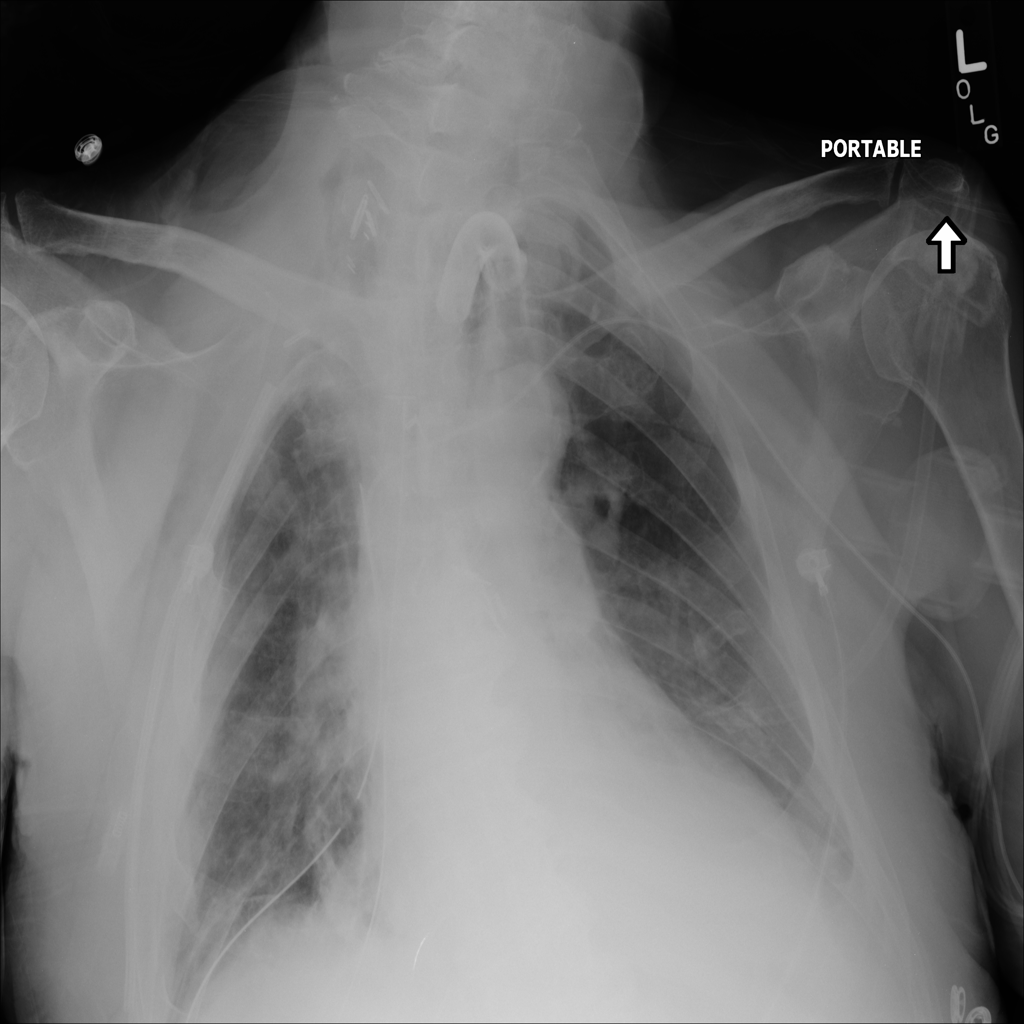

PAT-B9C3 · IMG-000Atelectasis

PAT-B9C3 · IMG-000

AP